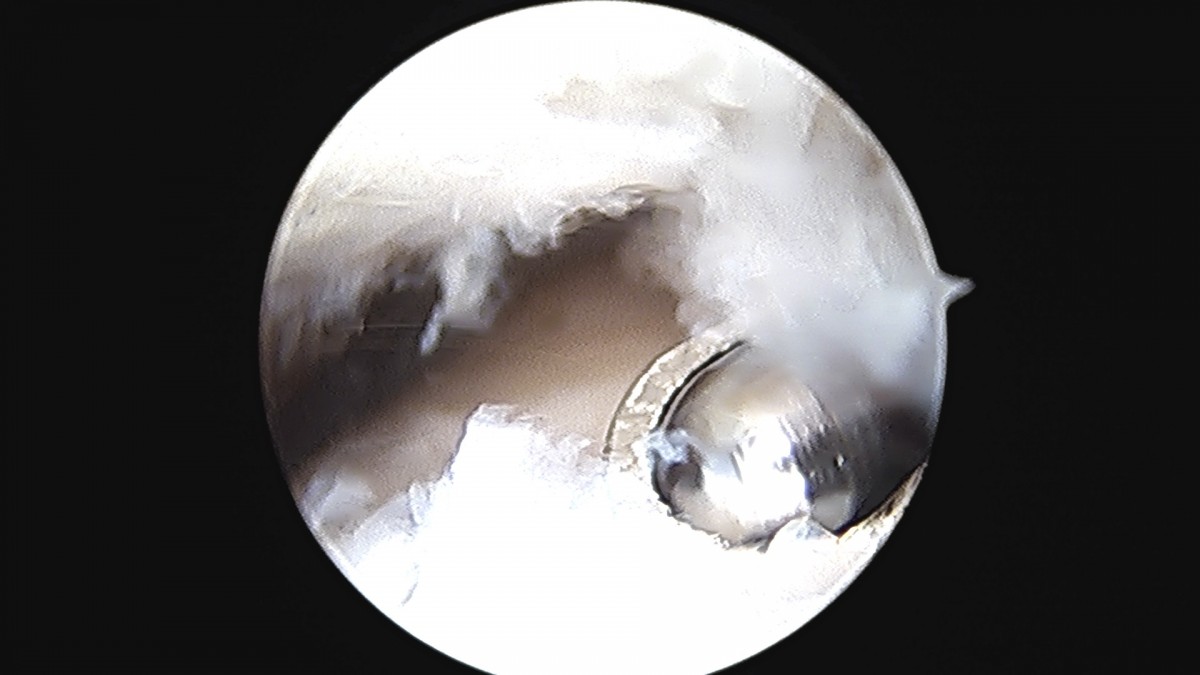

정지영원장님 발목 변연절제술 권공O 환자

작성자 최고관리자 댓글 0건 조회 743회 작성일 25-09-16 17:04